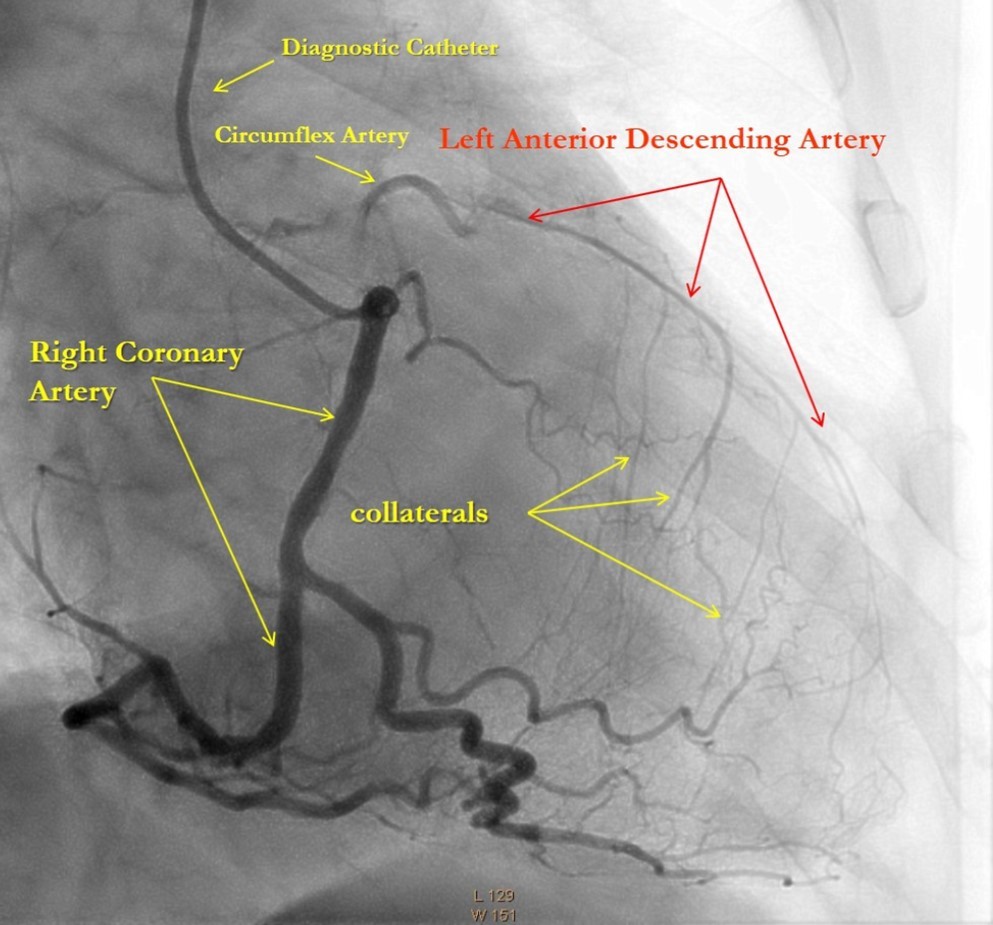

After medical treatment and comparable improvement in the patient's condition, expected risks were re-evaluated. After consulting with the patient and family members (they did not agree to the operation based on past experience) it was resolved to perform repeated CAG and to attempt revascularization of the LAD artery, (stenting). However, repeated CAG additionally revealed chronic 100% occlusion of the LMCA (Figure 1), and also CX occlusion, which was unexpected, and thereby significantly decreasing the likelihood of procedural success. In this case, the patient's heart was supplied only through the right coronary artery, which partially supplies the occluded left anterior descending and circumflex arteries through the contralateral collateral blood flow (Figure 2). Acute LMCA occlusion in most of the cases is fatal and survival is possible only in patients with a dominant RCA providing sufficient collateral formation.

Figure 2.Right Coronary Artery with developed right-to-left collaterals.